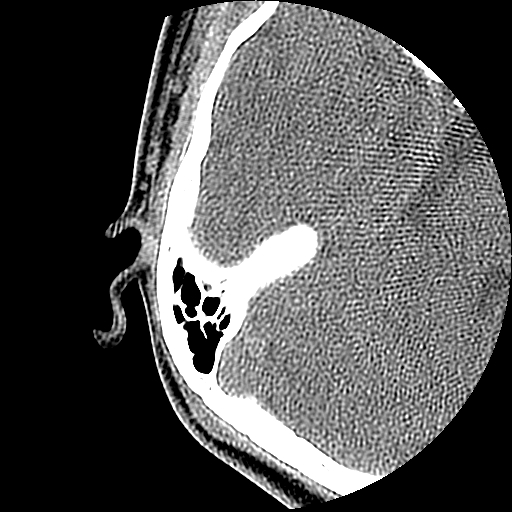

以下是引用随光逐影在2009-8-19 7:25:00的发言:[br]右侧慢性中耳乳突炎,右侧中耳腔及外耳道肉芽肿或胆脂瘤形成。